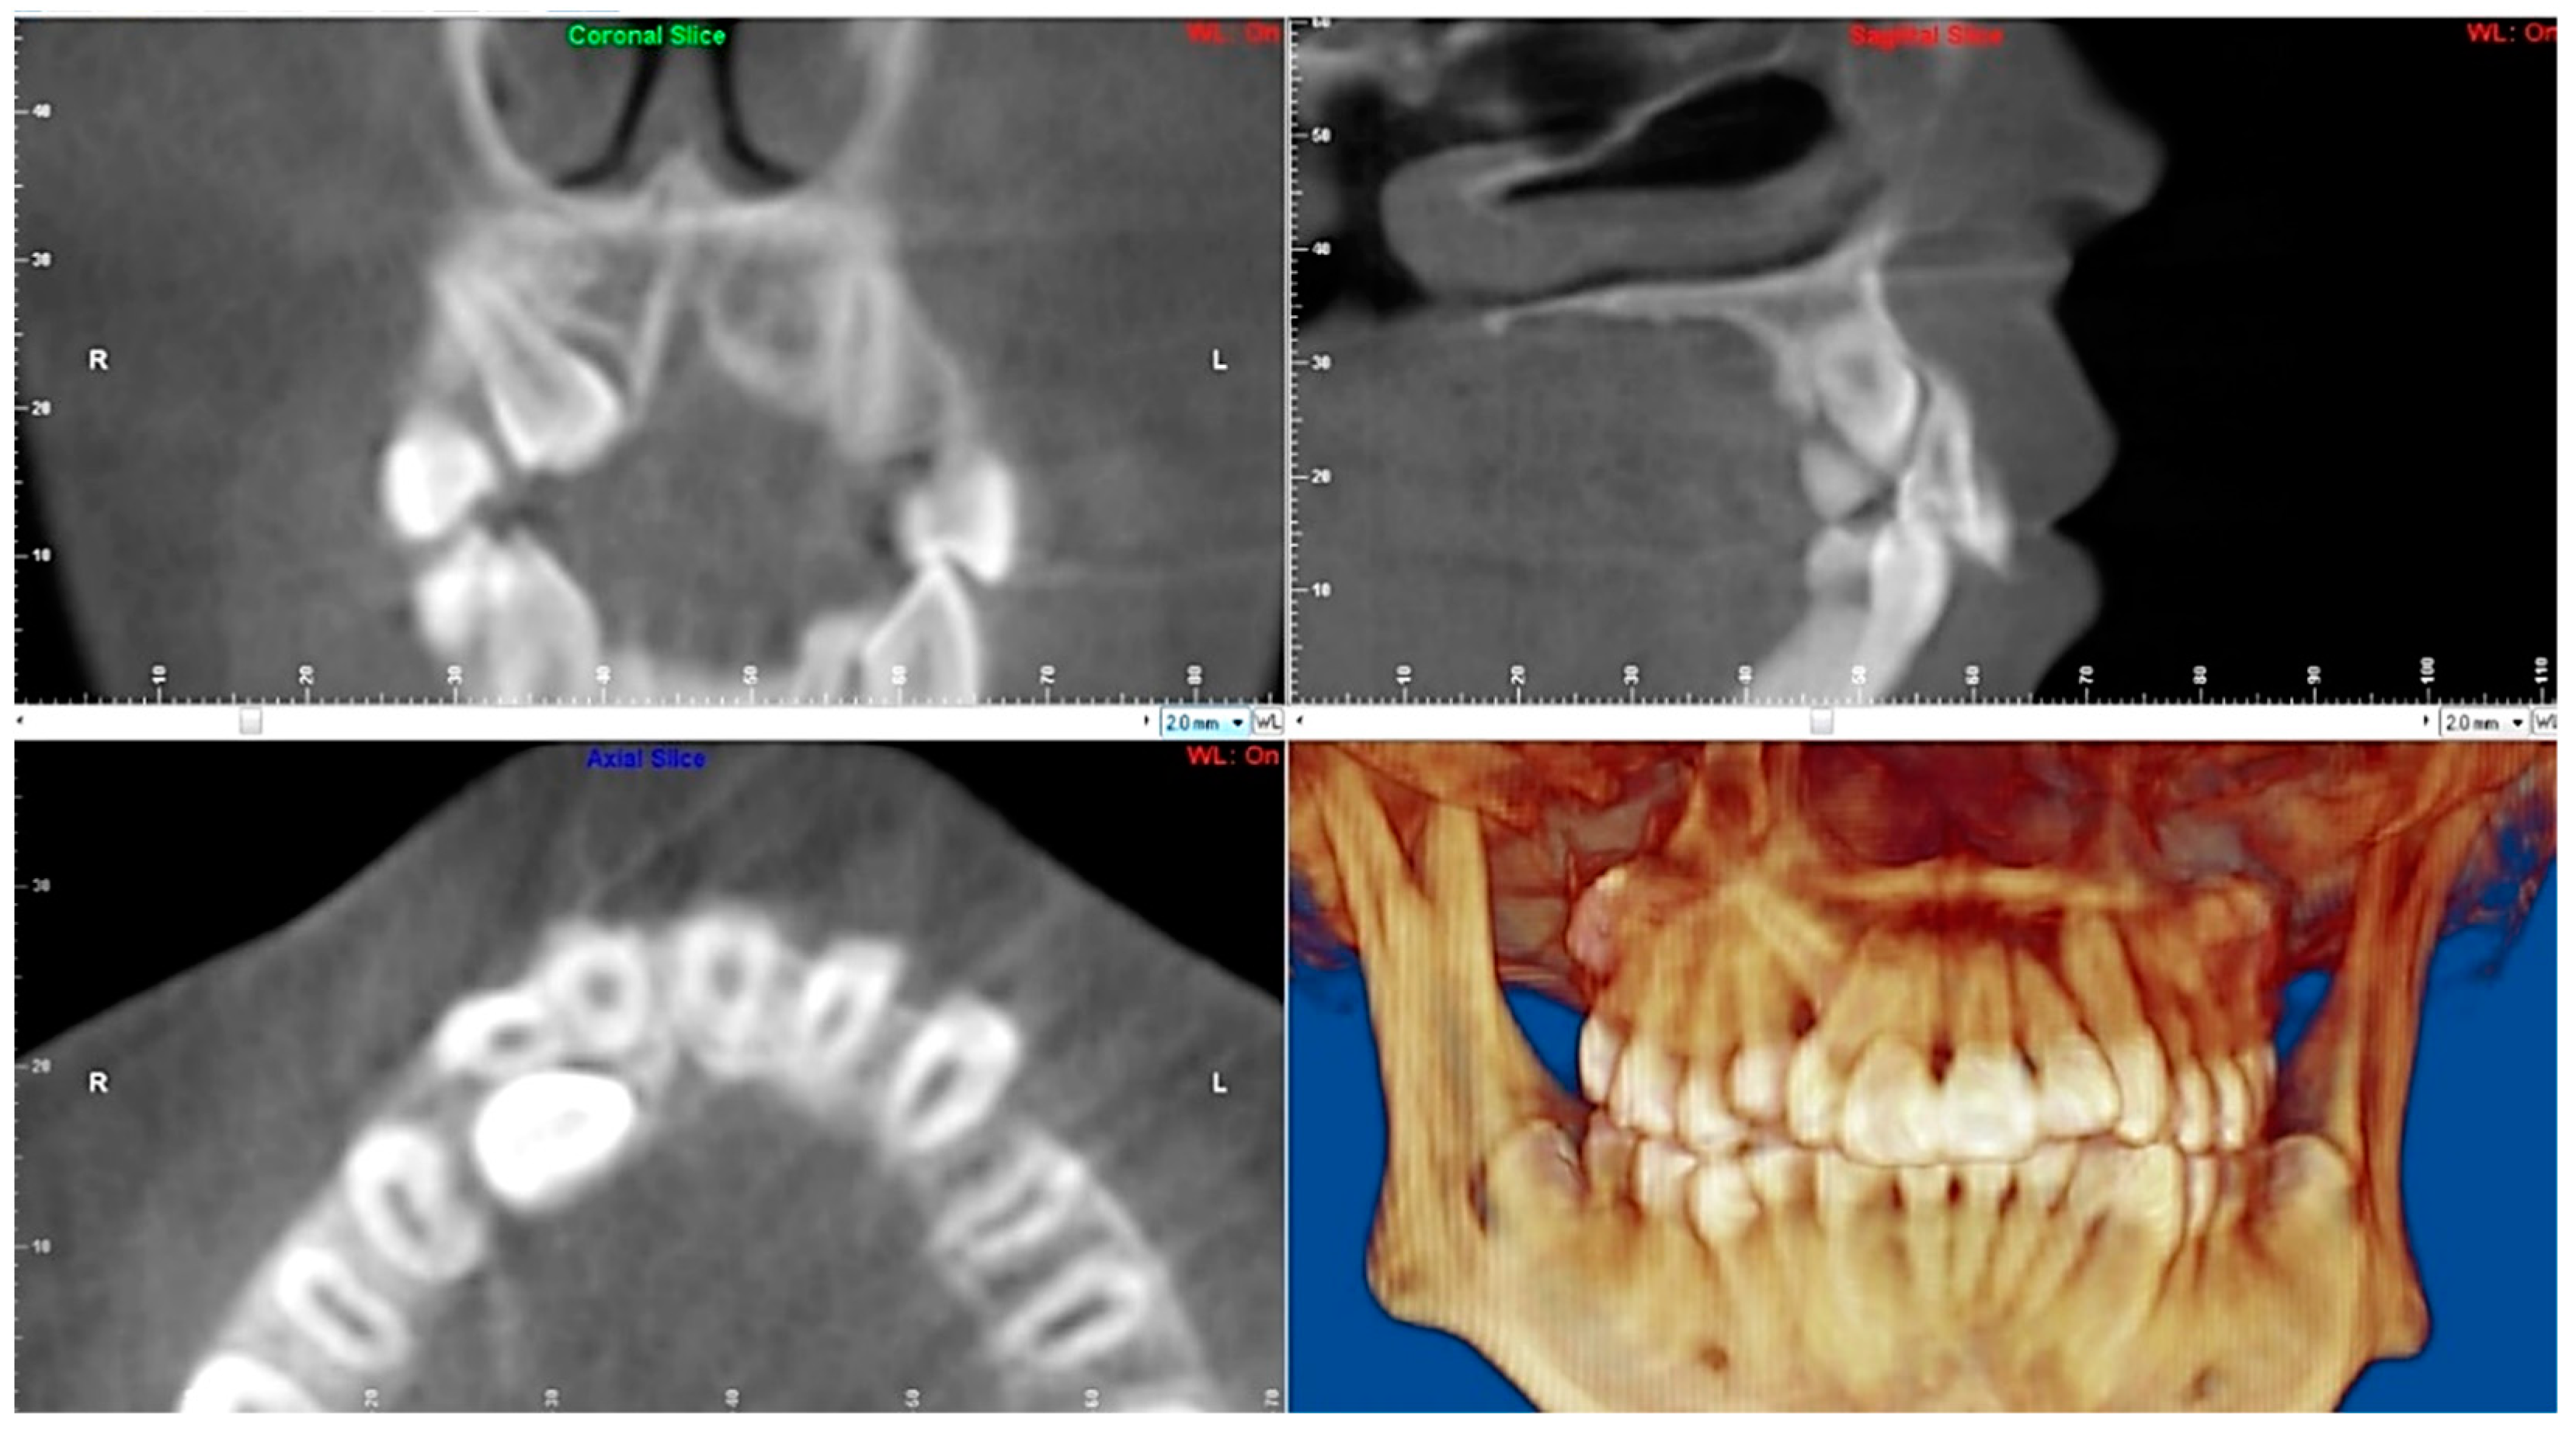

- Evaluation of impacted teeth, a common indication of CBCT in orthodontics. The advantages of CBCT include assessment of the tooth location and position, the stage of development, and status of adjacent teeth. CBCT is justified in these cases, because CBCT has the capability of evaluating the impacted teeth and adjacent structures more accurately than 2D conventional imaging. The benefit–risk ratio is favorable, especially if the CBCT volume is collimated to the impacted tooth. Figure 1, Figure 2, Figure 3 and Figure 4 show an example of impacted maxillary canines, and their proximity to the maxillary lateral incisors. Figure 1 shows an intraoral photograph. The benefit of CBCT acquisition in this case includes the ability to visualize the canines and the lateral incisors in three dimensions, which can be visualized in Figure 2 and Figure 3. In this case, the maxillary right lateral incisor exhibited external root resorption, a finding that would be difficult to see on a conventional 2D panoramic radiograph. Figure 4 shows a Maximum Intensity Projection of a panoramic view derived from the CBCT volume. This unique view is free of magnification, distortion, ghost images, and overlaps frequently seen in conventional 2D panoramic radiography.